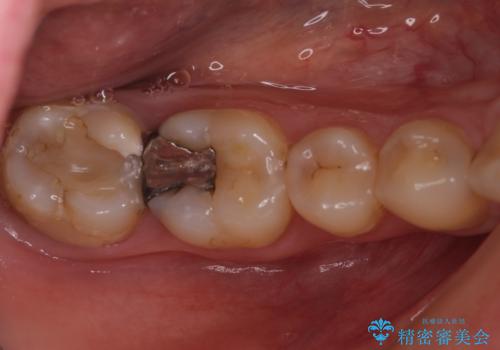

- 右上下の奥歯がむし歯でしみたり痛んだりするとのことで来院された患者様です。

下顎の奥歯は強い痛みを感じており、既に歯髄に不可逆的な炎症が起きていると診断されたため、根管治療の後にセラミッククラウンにて補綴治療を行うこととしました。

上顎の奥歯は最近銀歯による治療を行ったとのことでしたが、適合が不十分であり隙間からしみていたため、適合の良いゴールドインレーにて修復治療を行うこととしました。

下顎のむし歯は歯肉の中にまで及んでいたため、一部歯槽骨を削除し、歯肉縁上に健全歯質が位置するよう外科処置を併用しました。